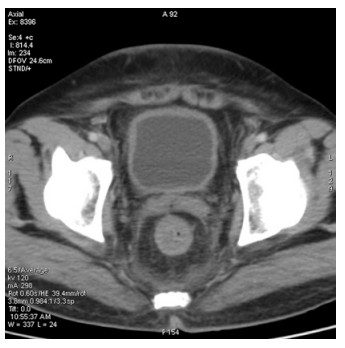

Abstract: Rectal malignancy is usually symptomatic due to its location, and most of the time presents with pain and bleeding due to its growth and ulceration. It is difficult to identify the primary as carcinoma or lymphoma based on symptoms only, as both have a similar presentation. As it presents the rarest form of histology, non-Hodgkin's lymphoma in the rectum is still difficult to diagnose initially, and its treatment is debatable. We describe the case of a 49-year-old male from Bangladesh with the same presentation. His treatment was delayed for more than a month as immunohistochemistry and staging delayed the final diagnosis. The disease was diagnosed as stage IE with the help of a positron emission tomography (PET)-CT scan, and due to the local progression the patient had a massive rectal bleeding that needed an urgent intervention. Radiotherapy was applied to stop the bleeding. Hypofraction followed by a conventional fraction of external beam radiotherapy (EBRT) with a total of 40 Gy was applied. Post-EBRT digital rectal examination showed no residual except scaring, and a PET scan was also negative for residual disease. Due to uncertainties and lack of any precious guideline, 6 cycles of adjuvant chemotherapy with the R-CHOP schedule were also completed. Without surgery, the combination of EBRT and chemotherapy helped to preserve the organ, and the patient has been disease free for more than 2.5 years since his treatment.